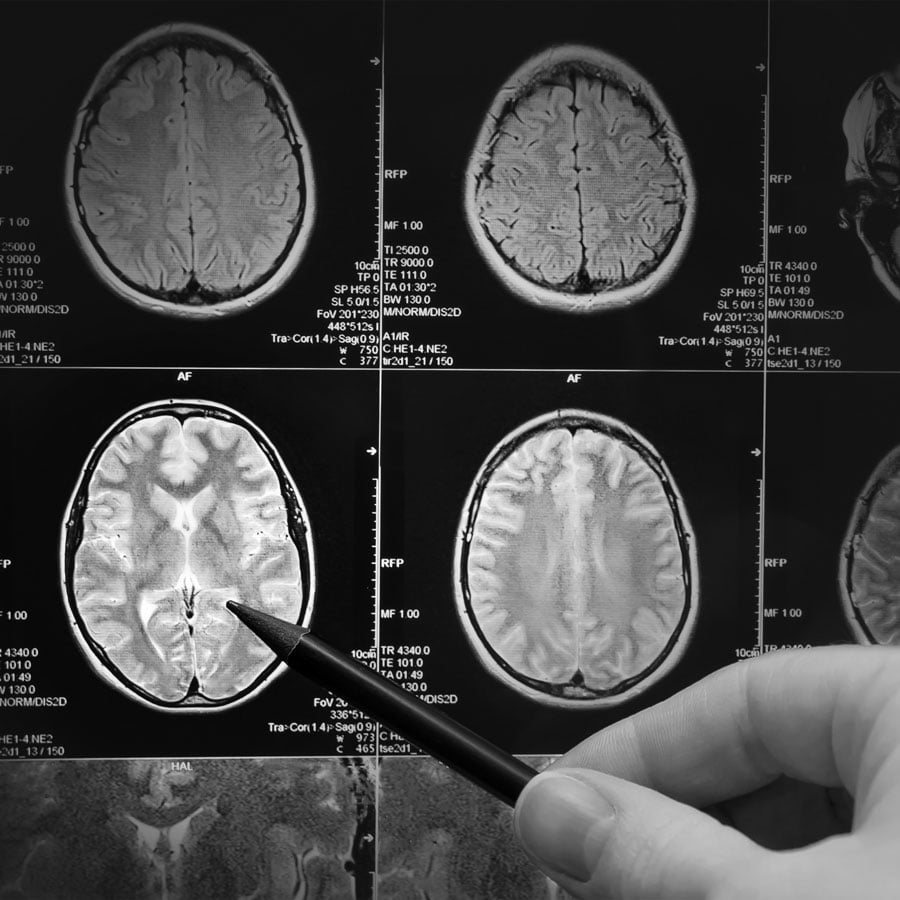

Diagnostic Imaging

Our Department is proud to offer:

- Magnetic Resonance Imaging (MRI)